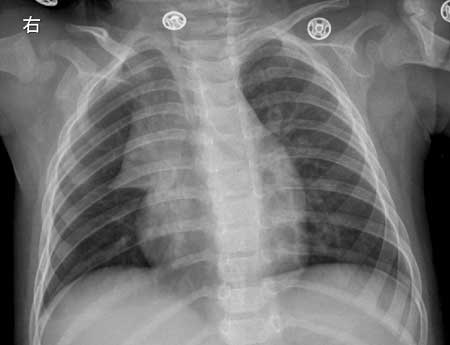

女,1岁,咳嗽1周。

摄片位置不太正,略呈左前斜,双肺纹理增多、模糊,右上纵隔阴影增宽,呈“船帆”状突向右侧肺野,下缘接近水平与心脏边缘构成切迹(胸腺角)。

诊断:1   支气管炎

2   正常小儿胸腺(典型),一岁以下的婴儿常易看到胸腺,系生理现象,左前斜位显示最清。

右上纵隔阴影增宽,呈“船帆”状突向右侧肺野,边缘光滑锐利,典型的小儿胸腺肥大。

由于胸腺在幼儿是重要的预防器官(胸腺t淋巴细胞能预防、阻挡病毒、细菌的侵犯),虽说2~3岁幼儿胸腺肥大常见,但多在感染及发烧时增大明显,而且随着病情的好转,可以有较快的动态变化。因此不能以一句生理现象一带而过,仔细前后比较对临床有参考价值。

“船帆”征系1周岁以内小儿胸腺x线影像,不是“胸腺肥大”或“胸腺增大”,而是正常的胸腺,只是在1周岁以内胸腺相对胸骨和纵隔来说更“宽大”,摄片时容易“露出”来。正如sdqzwyx所说“系生理现象”。

人出生时,胸腺只有14克-16克,到1周岁,胸腺30克左右,到青春期,胸腺发育到高峰,约35克-45克,以后随着年龄的增长而逐渐加速萎缩,约到50岁左右,这些胸腺大部分被脂肪代替。